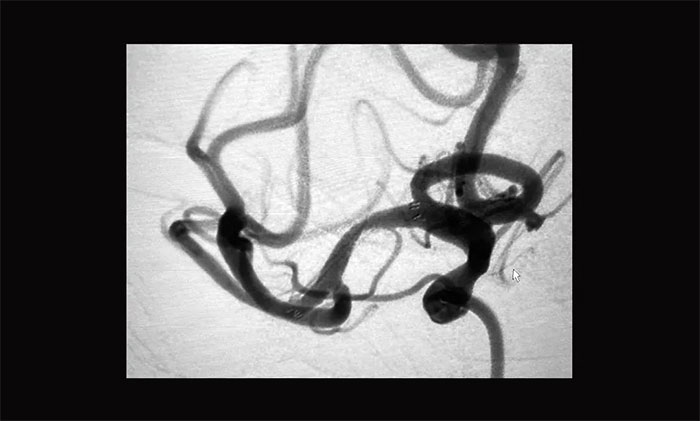

患者血管迂曲,張琪博士在周林華醫(yī)生協(xié)助下,經(jīng)過多次嘗試后,微導管、微導絲終于成功到達狹窄部位,順利進行球囊擴張并以支架拉栓,30分鐘后再次行造影提示右側(cè)大腦中動脈M1段無明顯改善,遂決定行右側(cè)大腦中動脈支架置入術。

支架導管到位右側(cè)大腦中動脈M2段上干,隨后經(jīng)微導管順利置入支架,造影見支架貼壁良好,完全覆蓋狹窄段,狹窄改善明顯,支架內(nèi)血流通暢,遠端血流良好,手術順利完成。

▲ 術后DSA影像:右側(cè)大腦中動脈血流恢復

術后,患者意識清楚,語言流利,左上肢無力感消失,四肢活動自如,由于經(jīng)橈動脈造影,術后即可下床行走,無需制動24小時。復查顱腦CT未見出血及新發(fā)梗死,目前患者正在康復中。